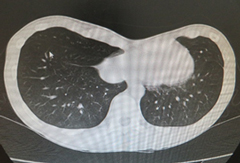

頚部リンパ管腫に対して硬化治療が奏功した一例

胎児超音波検査で頚部リンパ管腫を指摘されていた症例で、生後4か月時に病変が急速に増大して、呼吸困難で受診、外来で緊急気管挿管・緊急入院となりましたが、透視下に硬化療法を行ったところ、嚢胞性病変のほとんどが潰れて、治療後は腫れなくなり、元気に過ごしています。

圧迫して呼吸促迫になったため緊急気管挿管

(左頚部から縦隔に広がる病変)

病変内に注入し、透視で病変への広がりを

リアルタイムに確認。CT画像で指摘された

病変に一致して薬剤が広がった。

頚部の腫瘤はほとんど目立たなくなった。